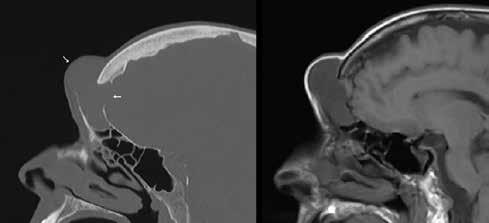

Figure 1. A: Axial CT image in bone windows demonstrates opacification of the frontal sinus with areas of thinning and frank erosion of the posterior cortex. B: Axial T1-weighted gadolinium-enhanced image at approximately the same level shows an avidly enhancing mass protruding intracranially through the bony defect with mild mass effect on the left frontal lobe. The mass abuts invade underlying enhancing dura mater (arrow).

The mass demonstrated intracranial extension, with much of the posterior cortex of the left frontal sinus eroded or thinned. The mass abutted the left frontal dura and created mild mass compression of the underlying brain. There was enhancement of the dura but no evidence of invasion or brain parenchymal involvement (figure 1). The midline component of the mass protruded anteriorly into the adjacent scalp soft tissues, with erosion and thinning of the anterior cortex (figure 2). A small portion of the mass appeared to extend through and widen the frontoethmoidal recess on the left. The inferior portion of the mass also eroded the roof of the left orbit, with extension into the extraconal orbital compartment and compression of the superior rectus muscle (figure 3).

Figure 2. A: Sagittal CT in bone windows demonstrates erosion of both the anterior and posterior cortex of the frontal sinus (arrows). B: Unenhanced T1-weighted sagittal MRI demonstrates the lowsignal mass protruding into the subcutaneous soft tissues, resulting in an obvious cosmetic deformity.

Figure 3. A: Coronal CT in bone windows demonstrates erosion of the left orbital roof (white arrow), with expansion of the left frontoethmoidal recess (white asterisk). B: Corresponding gadolinium-enhanced of mucocele formation.